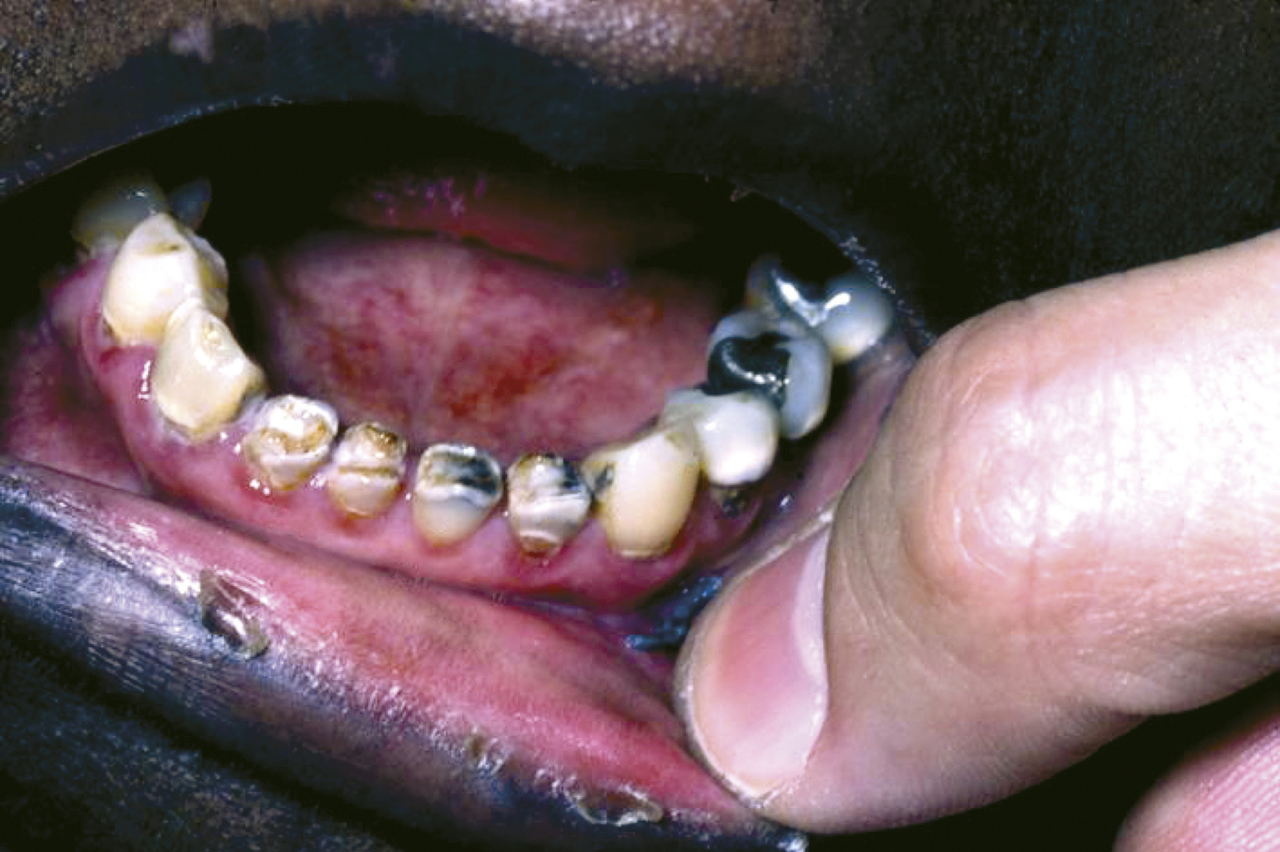

D’emblée, il convient de rechercher les complications de cette hyposialie (terme plus approprié que xérostomie) : signes d’une infection mycosique (candidose), d’infections bactériennes parodontales (gingivite, poches parodontales) et dentaires (multiples caries à progression rapide) [fig. 1 ]. Peu d’examens complémentaires sont utiles pour explorer la sècheresse salivaire en dehors de la mesure du flux salivaire (collection de salive totale par crachat) non indiquée dans les hyposialies médicamenteuses.

D’emblée, il convient de rechercher les complications de cette hyposialie (terme plus approprié que xérostomie) : signes d’une infection mycosique (candidose), d’infections bactériennes parodontales (gingivite, poches parodontales) et dentaires (multiples caries à progression rapide) [